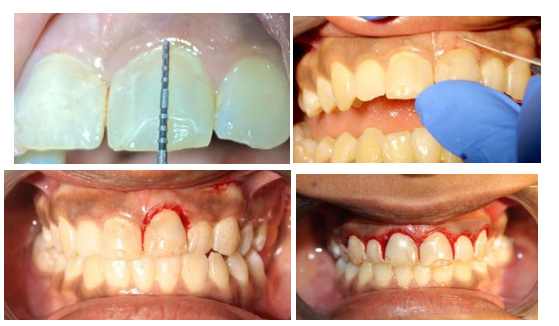

Examen intrabucal

En la evaluación intrabucal del paciente se observó una dentición permanente completa con todos los dientes erupcionados. Se notó la ausencia del diente 36 y de las piezas 46 y 47. Estas extracciones se llevaron a cabo en una etapa temprana de la vida del paciente, quien no recuerda el motivo específico de dichos procedimientos.

En cuanto a las restauraciones dentales, se identificaron cambios de coloración en la pieza 21, la cual presentaba una carilla de resina defectuosa con cambio de color y bordes irregulares, atribuibles a un tratamiento dental anterior. Similarmente, la pieza dental 12, con una asimetría morfológica notable en comparación con las piezas 12, 13, 22 y 23. A pesar de la coloración homogénea en las piezas dentales y una sonrisa clasificada como media, el paciente mostraba un estado de salud periodontal adecuado.

Se observaron también problemas en el contorno de los dientes anteriores y la arquitectura gingival, considerados inadecuados. La figura 3 ilustra los resultados del examen intrabucal:

Figura 3 Examen intrabucal de la paciente.

Nota. A-B. Erupción pasiva alterada tipo IA. C-D. Los contornos de los dientes anteriores y la arquitectura gingival son evaluados como inadecuados. E. Obturaciones defectuosas en las piezas 11 y 21 mostrando una alteración significativa en la coloración. F. Ausencia de piezas dentales en el maxilar inferior específicamente las piezas 36, 46 y 47.